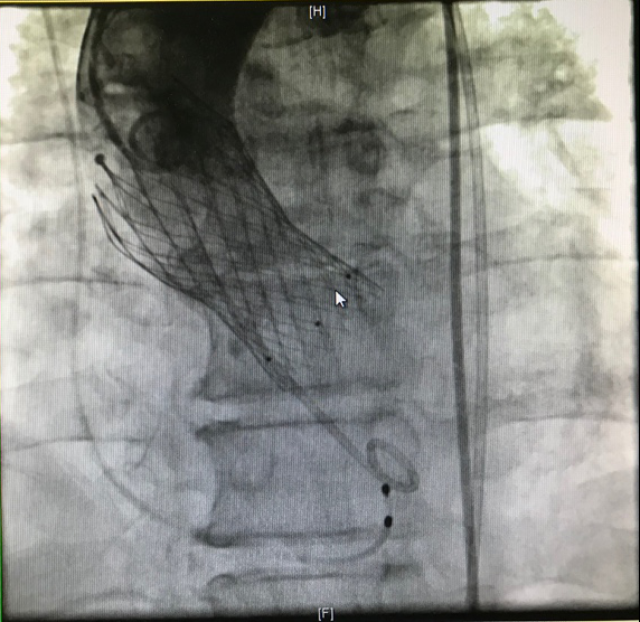

4月15日上午在吴永健教授指导下、心脏内科介入团队密切协作,成功为患者完成经皮主动脉瓣置换术,瓣膜位置良好,无瓣周漏、无跨瓣压差。术后患者血流动力学稳定,呼吸功能良好,达到撤机标准,随后顺利脱机,安全返回监护病房。